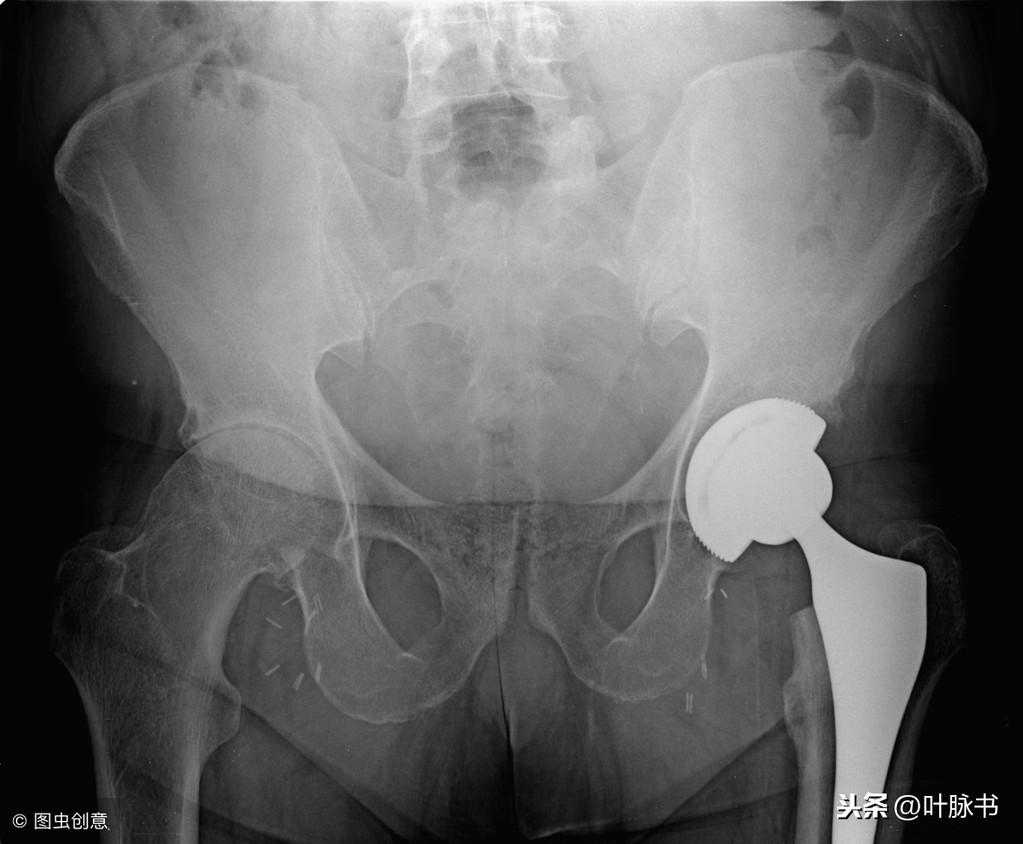

人造骨

人造骨是一种具有生物功能的新型无机金属材料,它类似于人骨和天然牙的性质的结构,人造骨可以依靠从人体体液补充某些离子形成新骨,可在骨骼接合界面发生分解、吸收、析出等反应,实现骨骼牢固结合